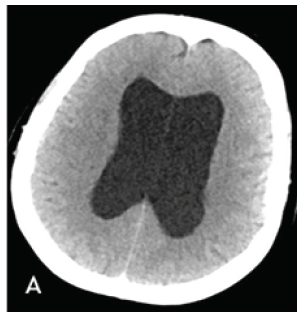

CT Brain was performed using a 128 slice Siemens Somtam Definition Edge scanner. Axial images were obtained with 5mm and 1mm slice thickness. Using the 3D MPR function on McKesson Radiology PACS station, reconstructions were performed. The sagittal reconstruction images demonstrated obstructive hydrocephalus with AW/D (Figure 1B).

Figure 1A: Axial 1mm CT slices acquired on Siemens Somatom Definition Edge scanner. Dilated bilateral lateral ventricles.